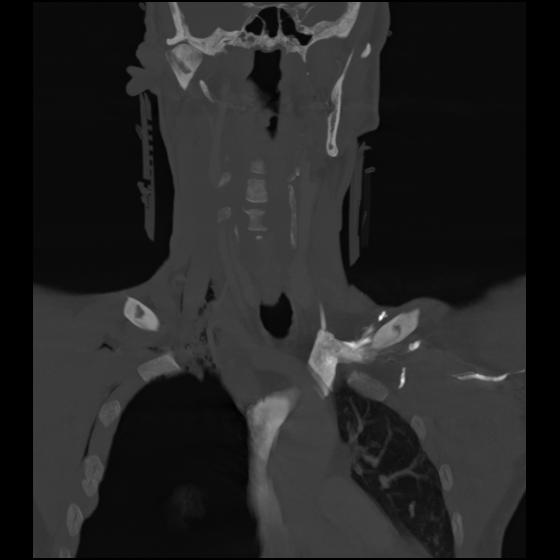

23 ANGIO,CE,Cor-MIP,5.000,ANGIO,Cor-MIP,